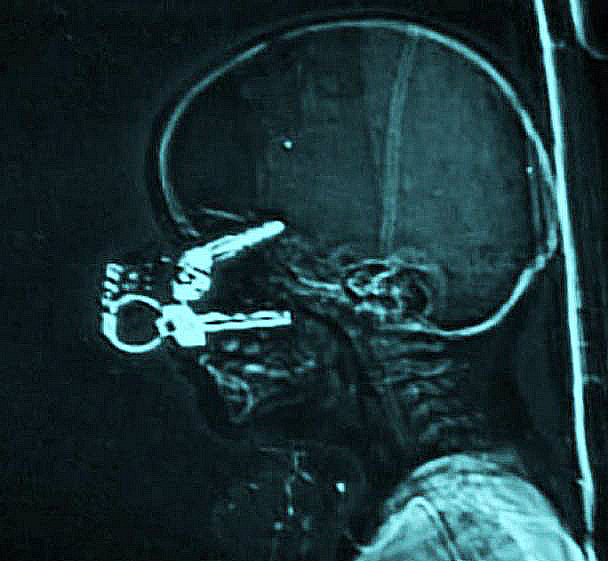

Keys

When playing at home, a 17-month-old boy fell on his parent's keys and one of them pierced his eyelid right into his brain. Shocking, right? The good news is that the boy fully recovered from the horrible injury.